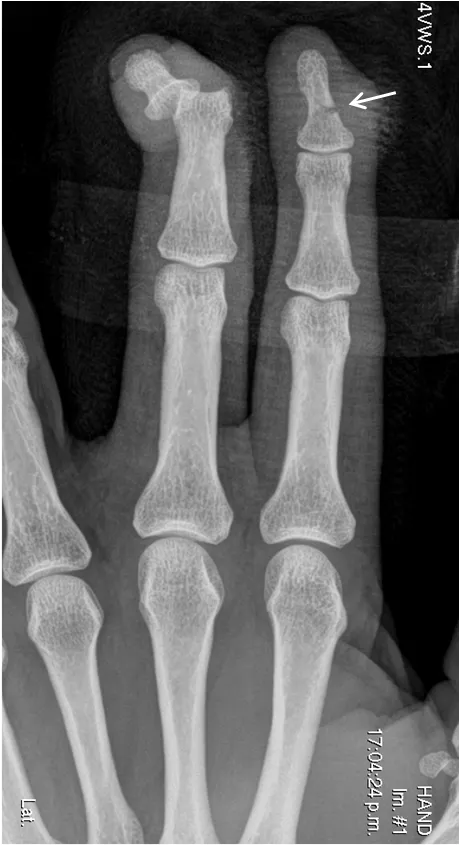

Radiografía del segundo y tercer dedo de la mano.

Se indicó la radiografía como primer método. En la radiografía se confirmaron una fractura transversal no desplazada, en la diáfisis de la falange ungueal del segundo dedo, y una luxación de la articulación IFD del tercer dedo.